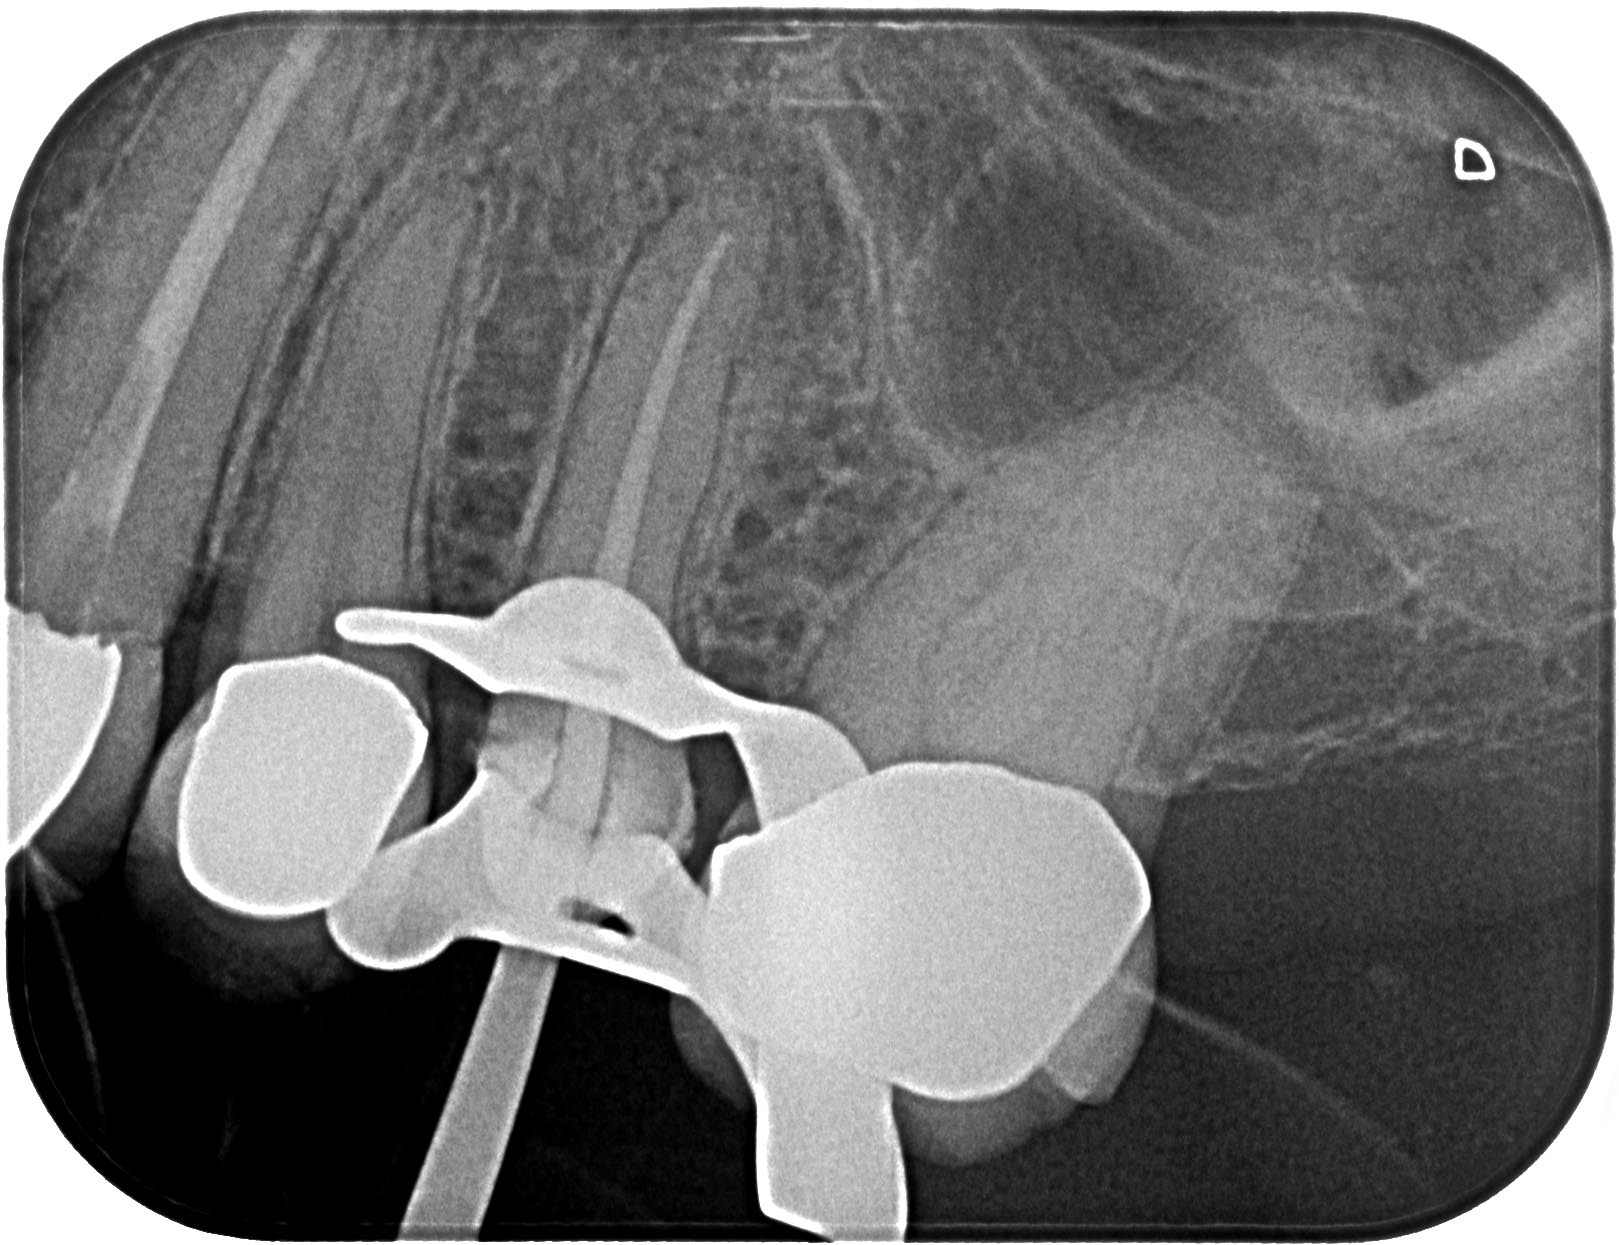

AA-12

1619 × 1245

Was braucht´s zur Heilung ?